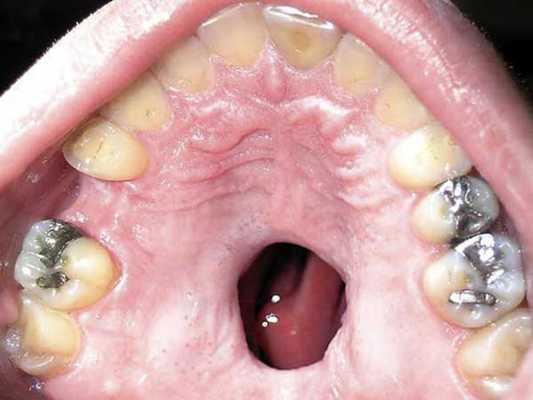

Для вторичного периода развития сифилиса на слизистых оболочках глотки и зева характерно одновременное возникновение аналогичных проявлений на кожных покровах - розеол и папул. Вторичные сифилиды слизистых оболочек содержат очень много трепонем (возбудителей сифилиса), и поэтому больные, которые имеют поражения слизистых зева, рта и глотки, представляют серьезную опасность для окружающих.

Заболевание может иметь эритематозную, эрозивную и папулёзную формы. Сифилитическая эритема представляет собой сплошное пятно, которое имеет резкие границы и синюшно-красный цвет. В некоторых случаях наблюдается незначительный отёк. Такие эритемы чаще всего локализуется на передних и задних нёбных дужках, языке, миндалинах и мягком нёбе.

Если эритема располагается на передних нёбных дужках, то она протекает под видом ангины. Такая ангина является одним из ранних вторичных проявлений сифилиса.

- Сифилитические папулы на слизистой - ключевое отличие. По краю они окружены красной каймой (в отличие от пятен гнойного налета при ангине).

- Папулы могут быть обнаружены не только на миндалинах, но и на языке, мягком небе, слизистой щек.

Папулы - это высыпания округлой формы, но без четких очертаний. Они могут проявиться на языке, небе, горле и миндалинах. Язвочки могут образовываться в одном месте и тем самым формировать крупные очаги. Если папула появилась на языке, на этом участке атрофируются чувствительные сосочки, появляется налет, под поверхностью которого скрываются воспаленные ткани красного цвета.

Розеолы немного похожи на папулы. Они представляют собой пятна, которые чаще всего появляются возле зубов, на небе и миндалинах. Из-за ярко-красного цвета розеолы выделяются на фоне слизистой оболочки полости рта. Они не доставляют пациенту особого дискомфорта, поэтому пока не появятся папулы, человек может даже не подозревать о заражении сифилитической инфекцией.